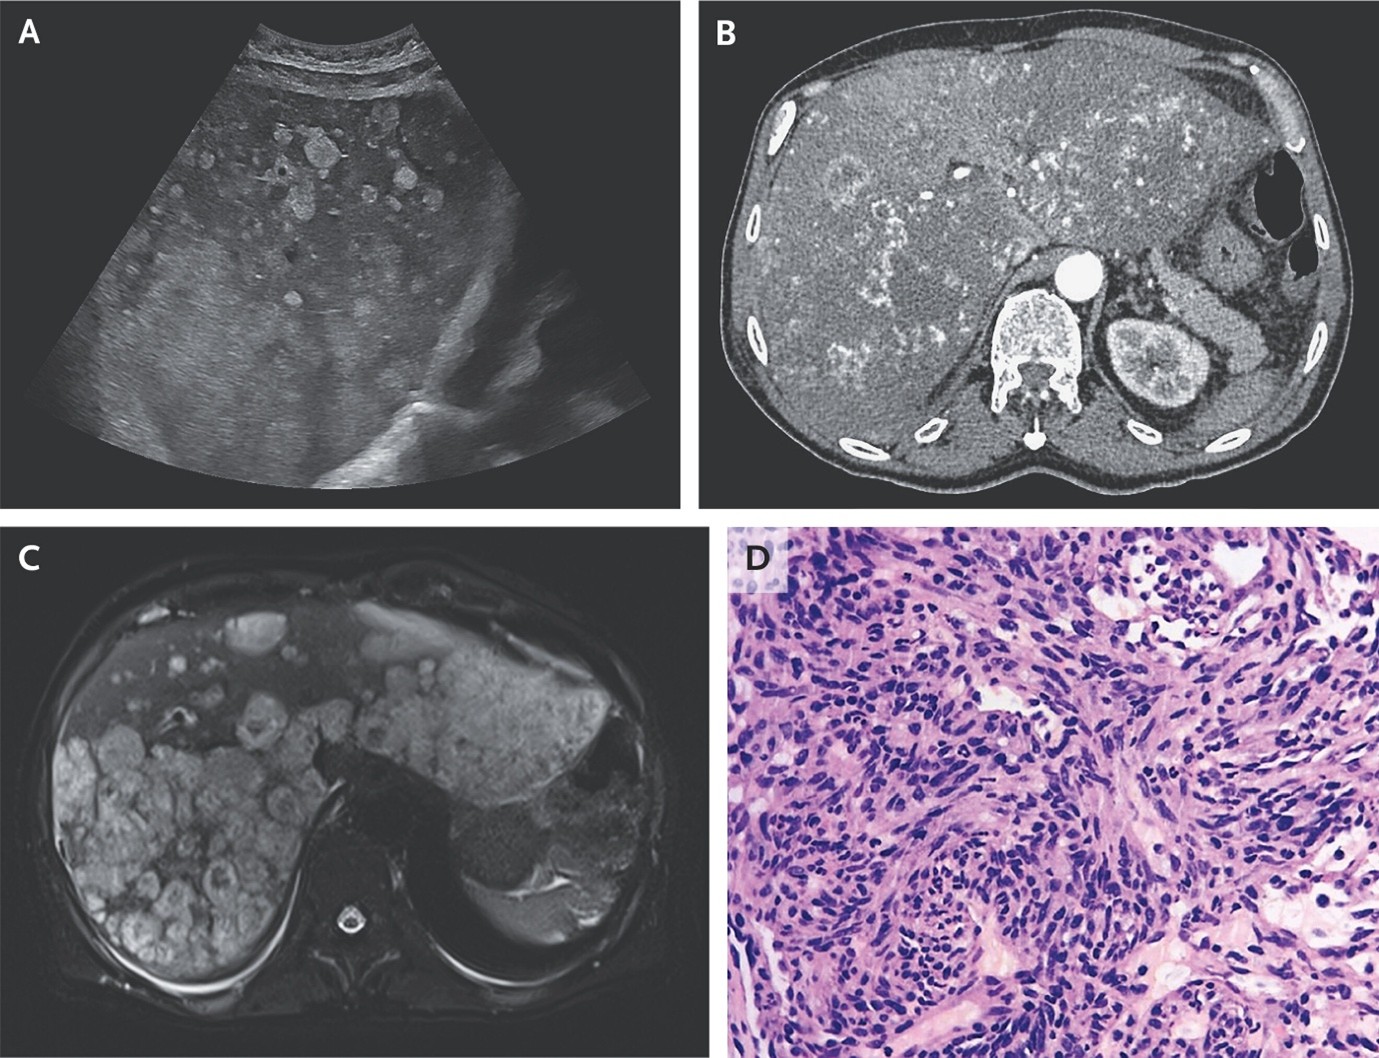

(10). Hepatic Angiosarcoma

Nicola Mumoli, Published February 7, 2026, N Engl J Med 2026;394: e11, DOI: 10.1056/NEJMicm2514897, VOL. 394 NO. 7

Abstract

A 60-year-old man presented with a 15-day history of generalized weakness and right upper abdominal pain. Imaging studies revealed diffuse disruption of the hepatic architecture by hyperechoic nodules and areas of necrosis and hemorrhage.